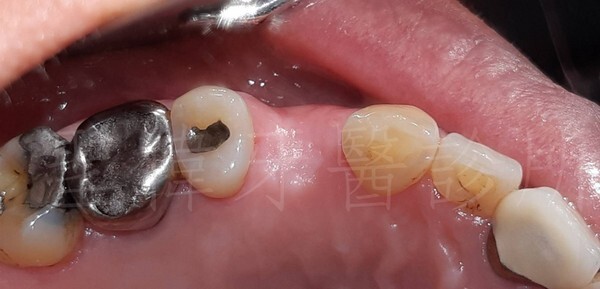

▼植牙之前的照片

雖然講話是不會漏風

不過一開口就蠻明顯會看的到